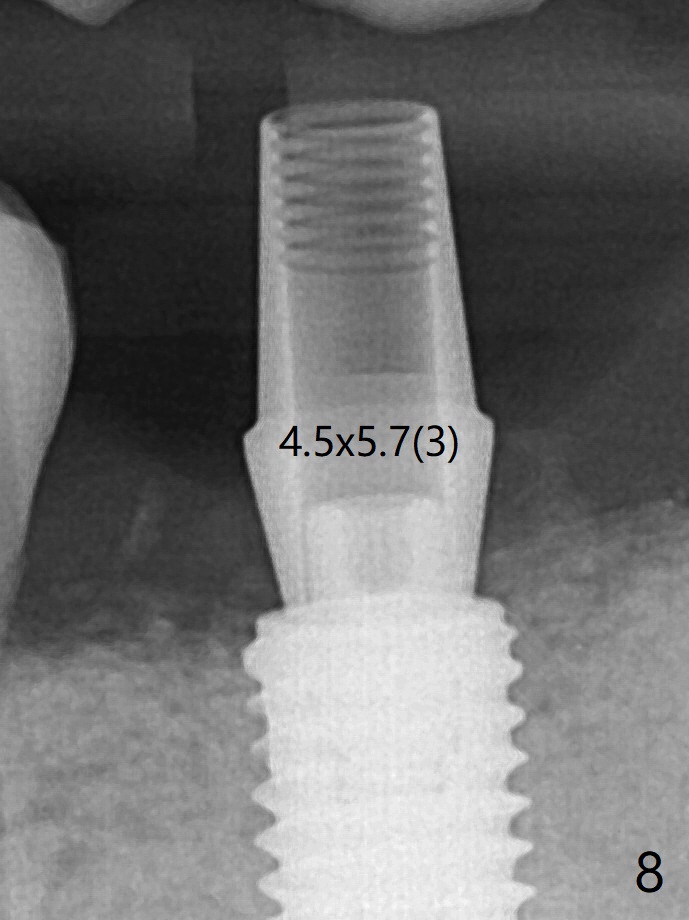

小一号基台仿佛完全就位(图八(咬翼片);图七(根尖片,可能失真)),但是临床上没有听到清脆声音(可能软硬组织阻挡)。随着时间推移,远中牙槽嵴吸收,当松动基台螺丝再次拧紧,可能会真正完全就位,必须拍摄完美咬翼片证实。这种植体芯(body, not threads)特别厚内部结构看不清楚。